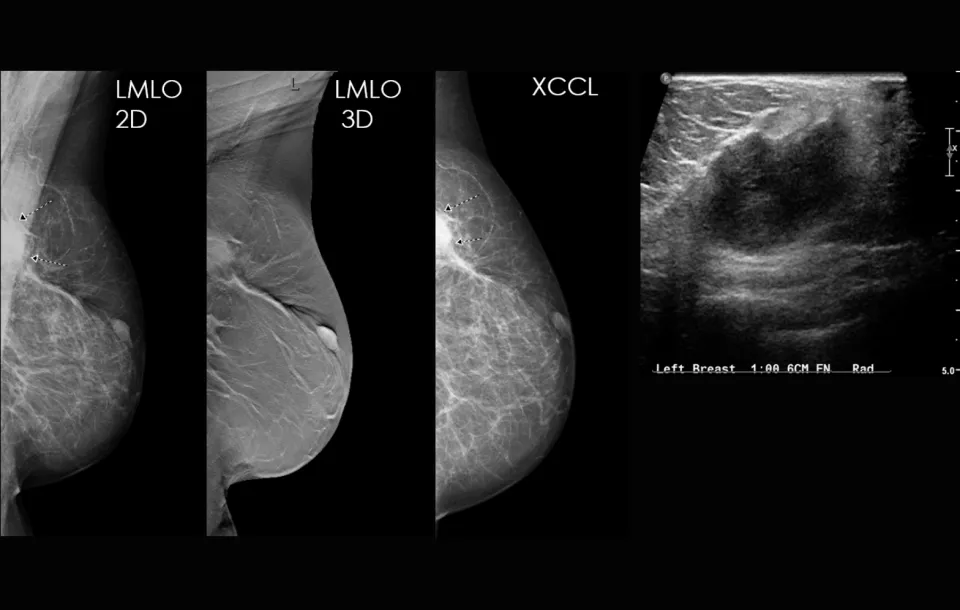

Compare the findings on the mammogram to the ultrasound

Recognize key characteristics of findings on both mammograms and ultrasounds, enhancing diagnostic capabilities

Case study review: correlating complex mammography studies to ultrasound findings